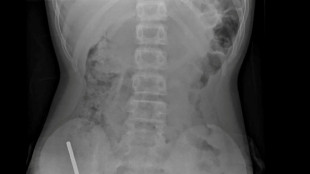

Surgeons remove up to 100 magnets from N. Zealand teen's gut

A 13-year-old boy in New Zealand swallowed up to 100 high-power magnets he bought on Temu, forcing surgeons to remove tissue from his intestines, doctors said on Friday.